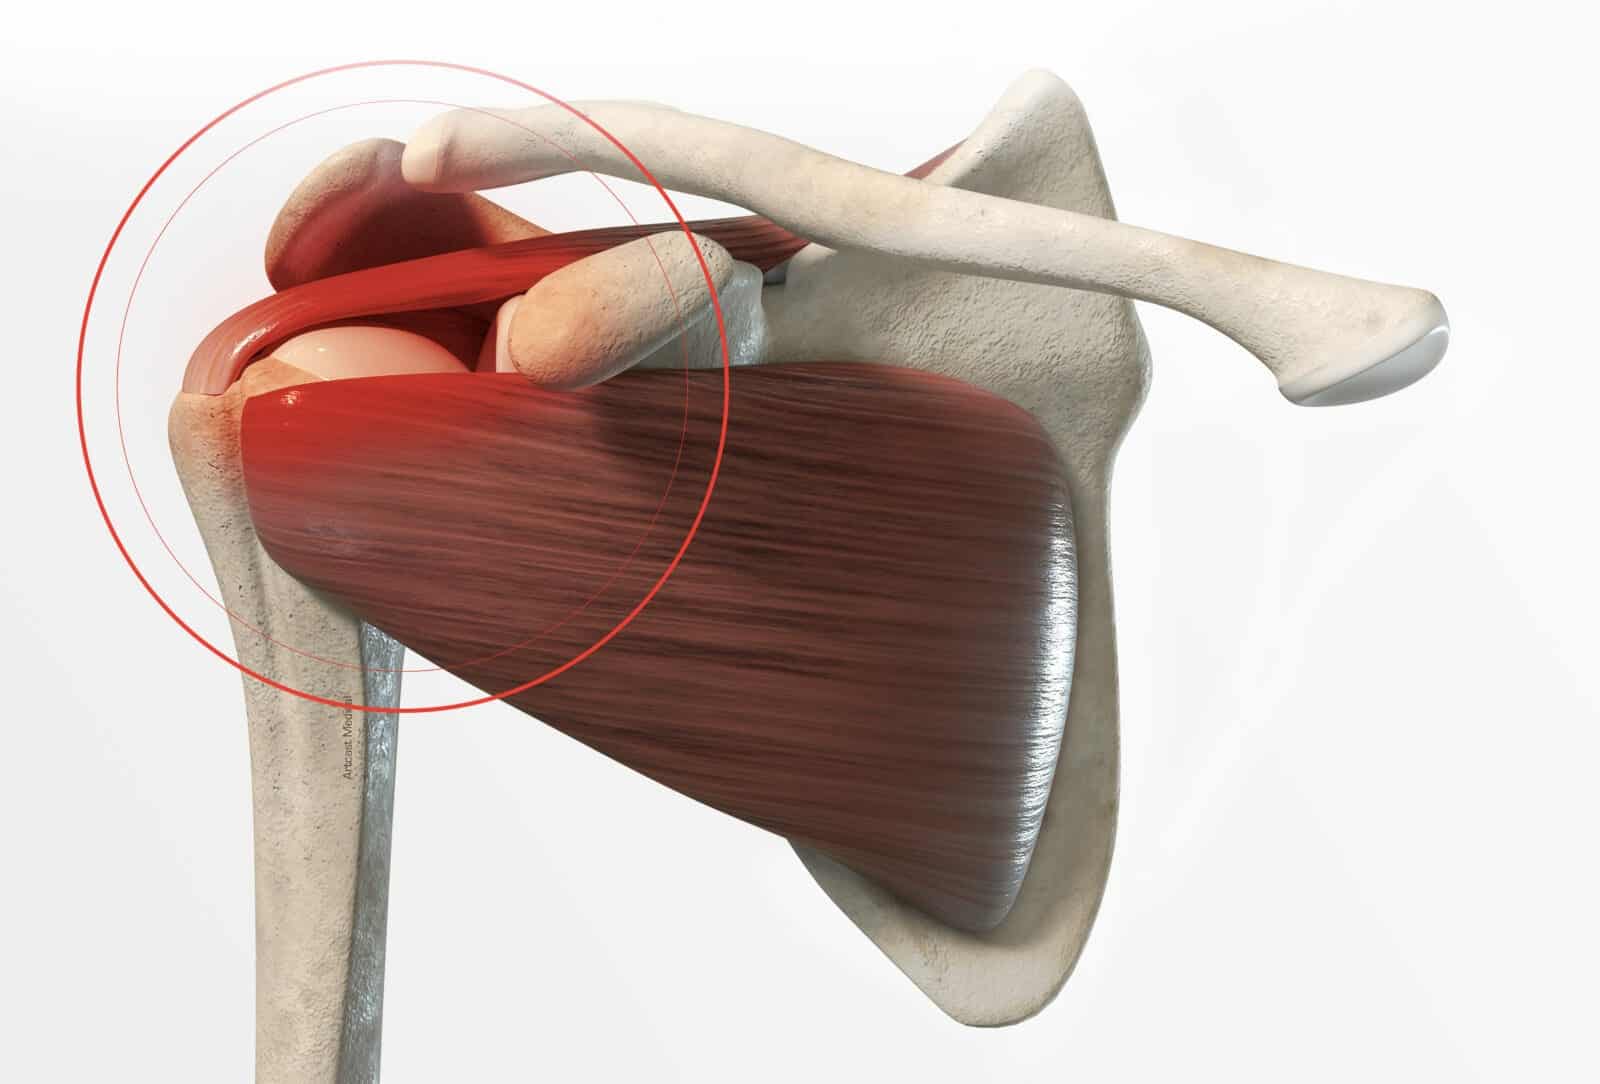

اختناق الأوتار الدوارة Rotator Cuff Impingement يحدث عندما تضغط العظام المحيطة بالكتف على الأوتار أثناء تحريك الذراع، خصوصًا عند رفع الذراع إلى الأعلى أو تحريكها جانبًا ويعد هذا الاحتكاك سببًا رئيسيًا لالتهاب الأوتار وقد يتفاقم مع التقدم في العمر أو مع الإفراط في استخدام الكتف في الرياضات التي تتطلب حركات متكررة فوق مستوى الرأس، ويصاحب الاختناق عادة شعور بالألم أثناء الحركة، ضعف في الكتف، وأحيانًا الطقطقة أو الاحتكاك، وإذا استمر الاختناق لفترات طويلة، فإنه يؤدي إلى تآكل الألياف وتضعف الأوتار تدريجيًا وهو ما يمهد الطريق لتمزق الأوتار الدوارة.

ما هي العلاقة بين الاختناق والتمزق؟

يعد الاختناق المزمن للأوتار الدوارة من العوامل الرئيسة المؤدية إلى تمزق جزئي أو كامل للأوتار، فالتعرض المستمر للاحتكاك يضعف ألياف الأوتار تدريجيًا، وتظهر الدراسات الطبية أن الأشخاص الذين يعانون من اختناق الأوتار لفترات طويلة دون علاج يواجهون خطر تمزق بنسبة تتراوح بين 30% و50% على المدى الطويل، وغالبًا ما يكون التمزق في أوتار العضلة فوق الشوكة (Supraspinatus) لأنها تقع مباشرة تحت منطقة الضغط، ويبدأ التمزق عادة كتمزق صغير جزئي ثم يتطور تدريجيًا إلى قطع كامل، مما يقلل قدرة الكتف على رفع الذراع وحمل الأوزان، ويصاحبه الألم المستمر وضعف العضلات.

العوامل التي تزيد من خطر القطع